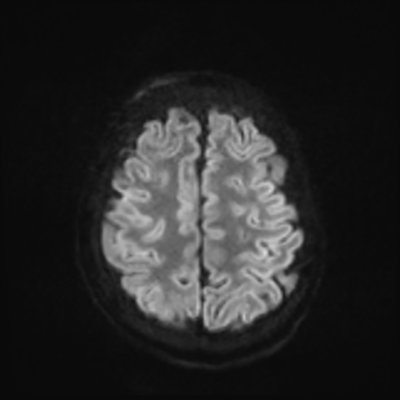

MRI brain (DWI)

You can clearly see diffuse cortical and basal ganglia diffusion restriction, and that of his deep cerebellar nuclei as well. The right occipital lobe abnormalities are a little more prominent, but then you remember that he is known to have had a right occipital stroke weeks ago.